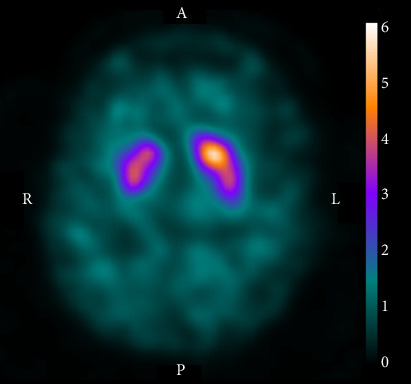

偏曲是缺血性脑卒中中一种罕见的表现,其病变通常位于对侧基底节区。其发病机制尚未完全阐明;然而,它可能与黑质纹状体功能障碍有关。在偏曲患者中,多巴胺转运-单光子发射计算机断层扫描显示对侧纹状体中示踪剂积累减少。此外,在特殊情况下,负责病变位于同侧大脑半球。本病例报告描述了一位84岁的男性,他表现为三周的间歇性,不自主和右肢体扭曲运动。体格检查,患者有右侧血瘀,无其他神经功能缺损。下肢的舞蹈动作比上肢更频繁,当他试图采取某种姿势或进行心算时,就会被激怒。怀疑脑卒中时进行的磁共振成像检测到在透镜状核后部和内囊后肢的右半球亚急性梗死。此外,DAT-SPECT显示右侧纹状体中示踪剂积累减少。他被诊断为腔隙性梗死后给予口服抗血小板药物。在接下来的8个月里,舞蹈动作逐渐减少,最终消失。考虑到出血与缺血性脑卒中在时间上的接近性,在透镜状核和内囊的病变被认为是诱发了同灶性出血。虽然在同裂孔出血患者中的DAT-SPECT发现尚未报道,但该病例提示黑质纹状体多巴胺功能障碍可能与同裂孔出血的发病机制有关。

Hemichorea is a rare manifestation of ischemic stroke whose lesion is typically located in the contralateral basal ganglia. Its pathomechanism has not been elucidated completely; however, it may be related to nigrostriatal dysfunction. In patients with hemichorea, dopamine transporter-single photon emission computed tomography (DAT-SPECT) reportedly displayed decreased tracer accumulation in the contralateral striatum. Moreover, in exceptional cases, responsible lesions were located in the ipsilateral cerebral hemisphere. This case report describes an 84-year-old man who presented with three weeks of intermittent, involuntary, and twisting movements in his right limbs. On physical examination, the patient had right-sided hemichorea without other neurological deficits. The choreic movements were more frequent in the lower limb than in the upper and provoked when he tried to take a certain posture or engaged in mental arithmetic. Magnetic resonance imaging performed on suspicion of stroke detected a right hemispheric subacute infarct in the posterior part of the lenticular nucleus and posterior limb of the internal capsule. Furthermore, DAT-SPECT revealed decreased tracer accumulation in the right striatum. He was administered oral antiplatelet medication after being diagnosed with lacunar infarction. The choreic movements gradually reduced over the next 8 months and eventually disappeared. The lesion in the lenticular nucleus and internal capsule was considered to have induced ipsilesional hemichorea, considering the temporal proximity between the hemichorea and ischemic stroke. Although DAT-SPECT findings in patients with ipsilesional hemichorea have not been reported, this case suggests that nigrostriatal dopamine dysfunction can contribute to the pathogenesis of ipsilesional hemichorea.